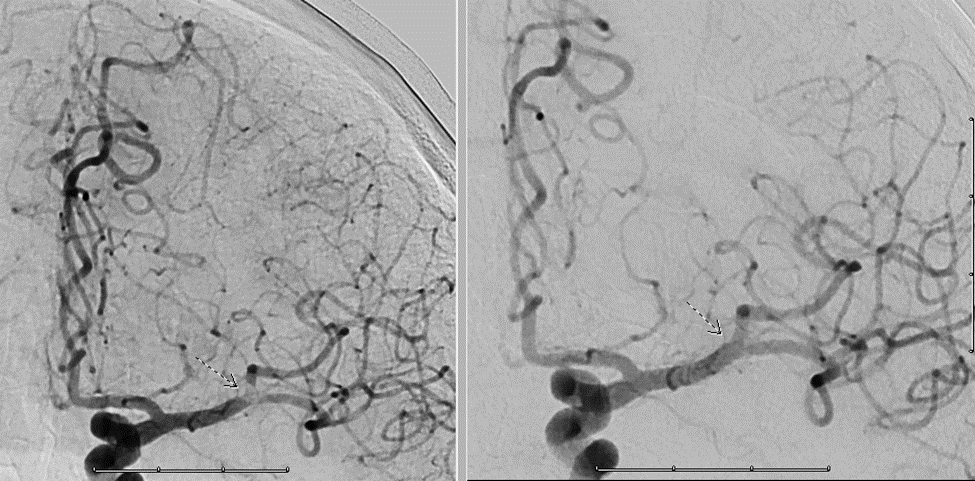

15/ The patient is kept in the ICU and ultimately undergoes #angiogram. Notice the area of perfusional deficit along the posterior MCA division:

16/ With some mild suction, @sudhakar_satti is able to suction a rubbery clot and the MCA looks much better post-procedure ๐Ÿ˜Ž

17/ The patient ๐Ÿšซ symptomatic recurrence since then! We suspect that the patient was intermittently occluding her anterior division with a fixed posterior division stenosis, and that is what was causing her symptoms: a ball-valve type phenomenon!